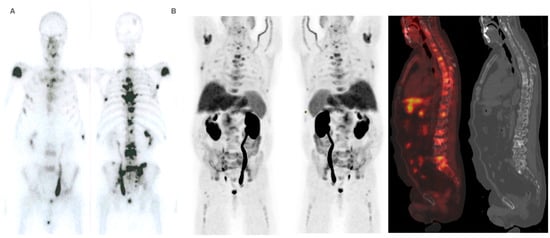

Performance status before 223Ra (p < 0.001), AP baseline levels (p < 0.001), and LDH (p = 0.033) were found to have a significant impact on OS (Figure 1), as well as other factors such as completion of treatment with 223Ra (p < 0.001). Regarding imaging variables, both the chi-square and the log-rank tests showed that derived FCH PET/CT variables had statistical significance. Thus, high tumor burden (p = 0.003), uptake of the most hypermetabolic lesion above the liver (p < 0.001), or STI in the FCH PET/CT study (p = 0.048) were associated with a lower median OS (Figure 2). Focusing on treatment response assessment, only interim studies (BS and FCH PET/CT) showed a significant association with OS, with data extracted from FCH PET/CT being slightly more robust compared to BS (p < 0.001 vs. p = 0.004, respectively) (Figure 3). The significant variables in the univariate analysis were included in the multivariate analysis for the OS and therapeutic failure end-points. In the former, the association of uptake of BM above the liver (p = 0.011), therapeutic failure (p = 0.001), or pathological baseline AP (p = 0.011) was highlighted as leading to lower OS. Table 8 details the results of the univariate Cox regression, and Table 9, Table 10 and Table 11 show the results of the log-rank test regarding OS.

Given the similar uptake properties of 223Ra and BS tracer in osteoblastic bone, a reasonable hypothesis is that metastatic disease with higher uptake on BS or 18F-NaF PET/CT compared to FCH PET/CT, is more likely to respond to 223Ra therapy, based on that increased choline levels can reflect on more aggressive tumors [39,40,41,42,43,44,47,48]. Ahmadzadehfar et al. [49] reported that when PSMA PET/CT is used as the gatekeeper in addition to BS, radionuclide therapy with 223Ra might be more effective and have more success regarding changes in the PSA, mainly because of better patient selection with the exclusion of patients with bone marrow involvement or STI. In our case, similar results were found with the combined use of FCH PET/CT and BS, as some of the FCH PET/CT variables had significant associations with OS. These included bone marrow infiltration (median 6 vs. 14 months; p < 0.001), uptake of the most hypermetabolic BM above the liver (median 10.5 vs. 16 months; p < 0.001), and STI (median 7 vs. 14 months; p = 0.048).

Moreover, our rate of SEs during 223Ra treatment was lower than the previously reported 15% by Palmedo et al. [31], which additionally defined no clear impact of bone health agents on SEs in similarity with our results. However, we found a significant association between SEs during and after treatment with 223Ra and the number of subsequent lines of treatment received, as well as the OS of these patients. These findings suggest that the presence of subsequent SEs increases in parallel with the survival of these patients as an inherent secondary effect of BM and bone metabolism disturbances due to age and androgen deprivation (Figure 7); in fact, any additional therapeutic line increased the risk by 42.7%. However, in multivariate analysis, only OS showed a significant association with SEs, as patients with OS longer than 12 months had 10.795 times increased risk of SEs. Additionally, a relationship was found between SEs, high tumor burden, and BM involvement in the FCH PET/CT but not in the BS, which could potentially be an important factor for selecting which patients could benefit from closer monitoring. The incidence of SEs in the present work (26%) was in accordance with respect to the 33% reported by the ALSYMPCA trial [56,57] and also by Bosch et al. [41] during and after 223Ra therapy (36.4% and 28.8% of patients selected with baseline-PSMA vs. baseline-CT, respectively), the latter possibly in the context of the presence of a higher volume of bone disease in the PSMA group (66.7% vs. 48.1%) or a shorter OS of the CT group.

Figure 5. Patient ≠ 1. A 71-year-old man, diagnosed with prostate adenocarcinoma Gleason Score 9 (4 + 5), underwent prostatectomy followed by adjuvant radiotherapy to the surgical bed due to early PSA progression. Three years after diagnosis, bone metastases were detected, prompting the start of systemic treatment lines (Enzalutamide and Docetaxel). 223Ra was administered as the third line. At the start of treatment, the patient was in good general condition (ECOG 0), experienced pain, and had baseline PSA levels of 50.7 ng/dL, AP of 377 IU/L, and LDH of 377 IU/L. Baseline BS (A) shows polymetastatic disease (>20 lesions) affecting both the axial and extra-axial skeleton. Baseline FCH PET/CT (B) shows the presence of mixed characteristic BM, bone marrow infiltration, and uptake of the most hypermetabolic BM higher than liver and soft tissue involvement at the pelvic lymph nodes. The concordance between both studies was moderate, defining FCH PET/CT more BM with respect to BS.

Cancers 16 02695 g005

Figure 6. Patient ≠ 1. PSA and AP showed a steady increase after 223Ra initiation. Clinical deterioration was observed after the third 223Ra administration. Interim BS (A) and FCH PET/CT (B) show disease progression. The patient died 6 months after starting treatment with 223Ra.